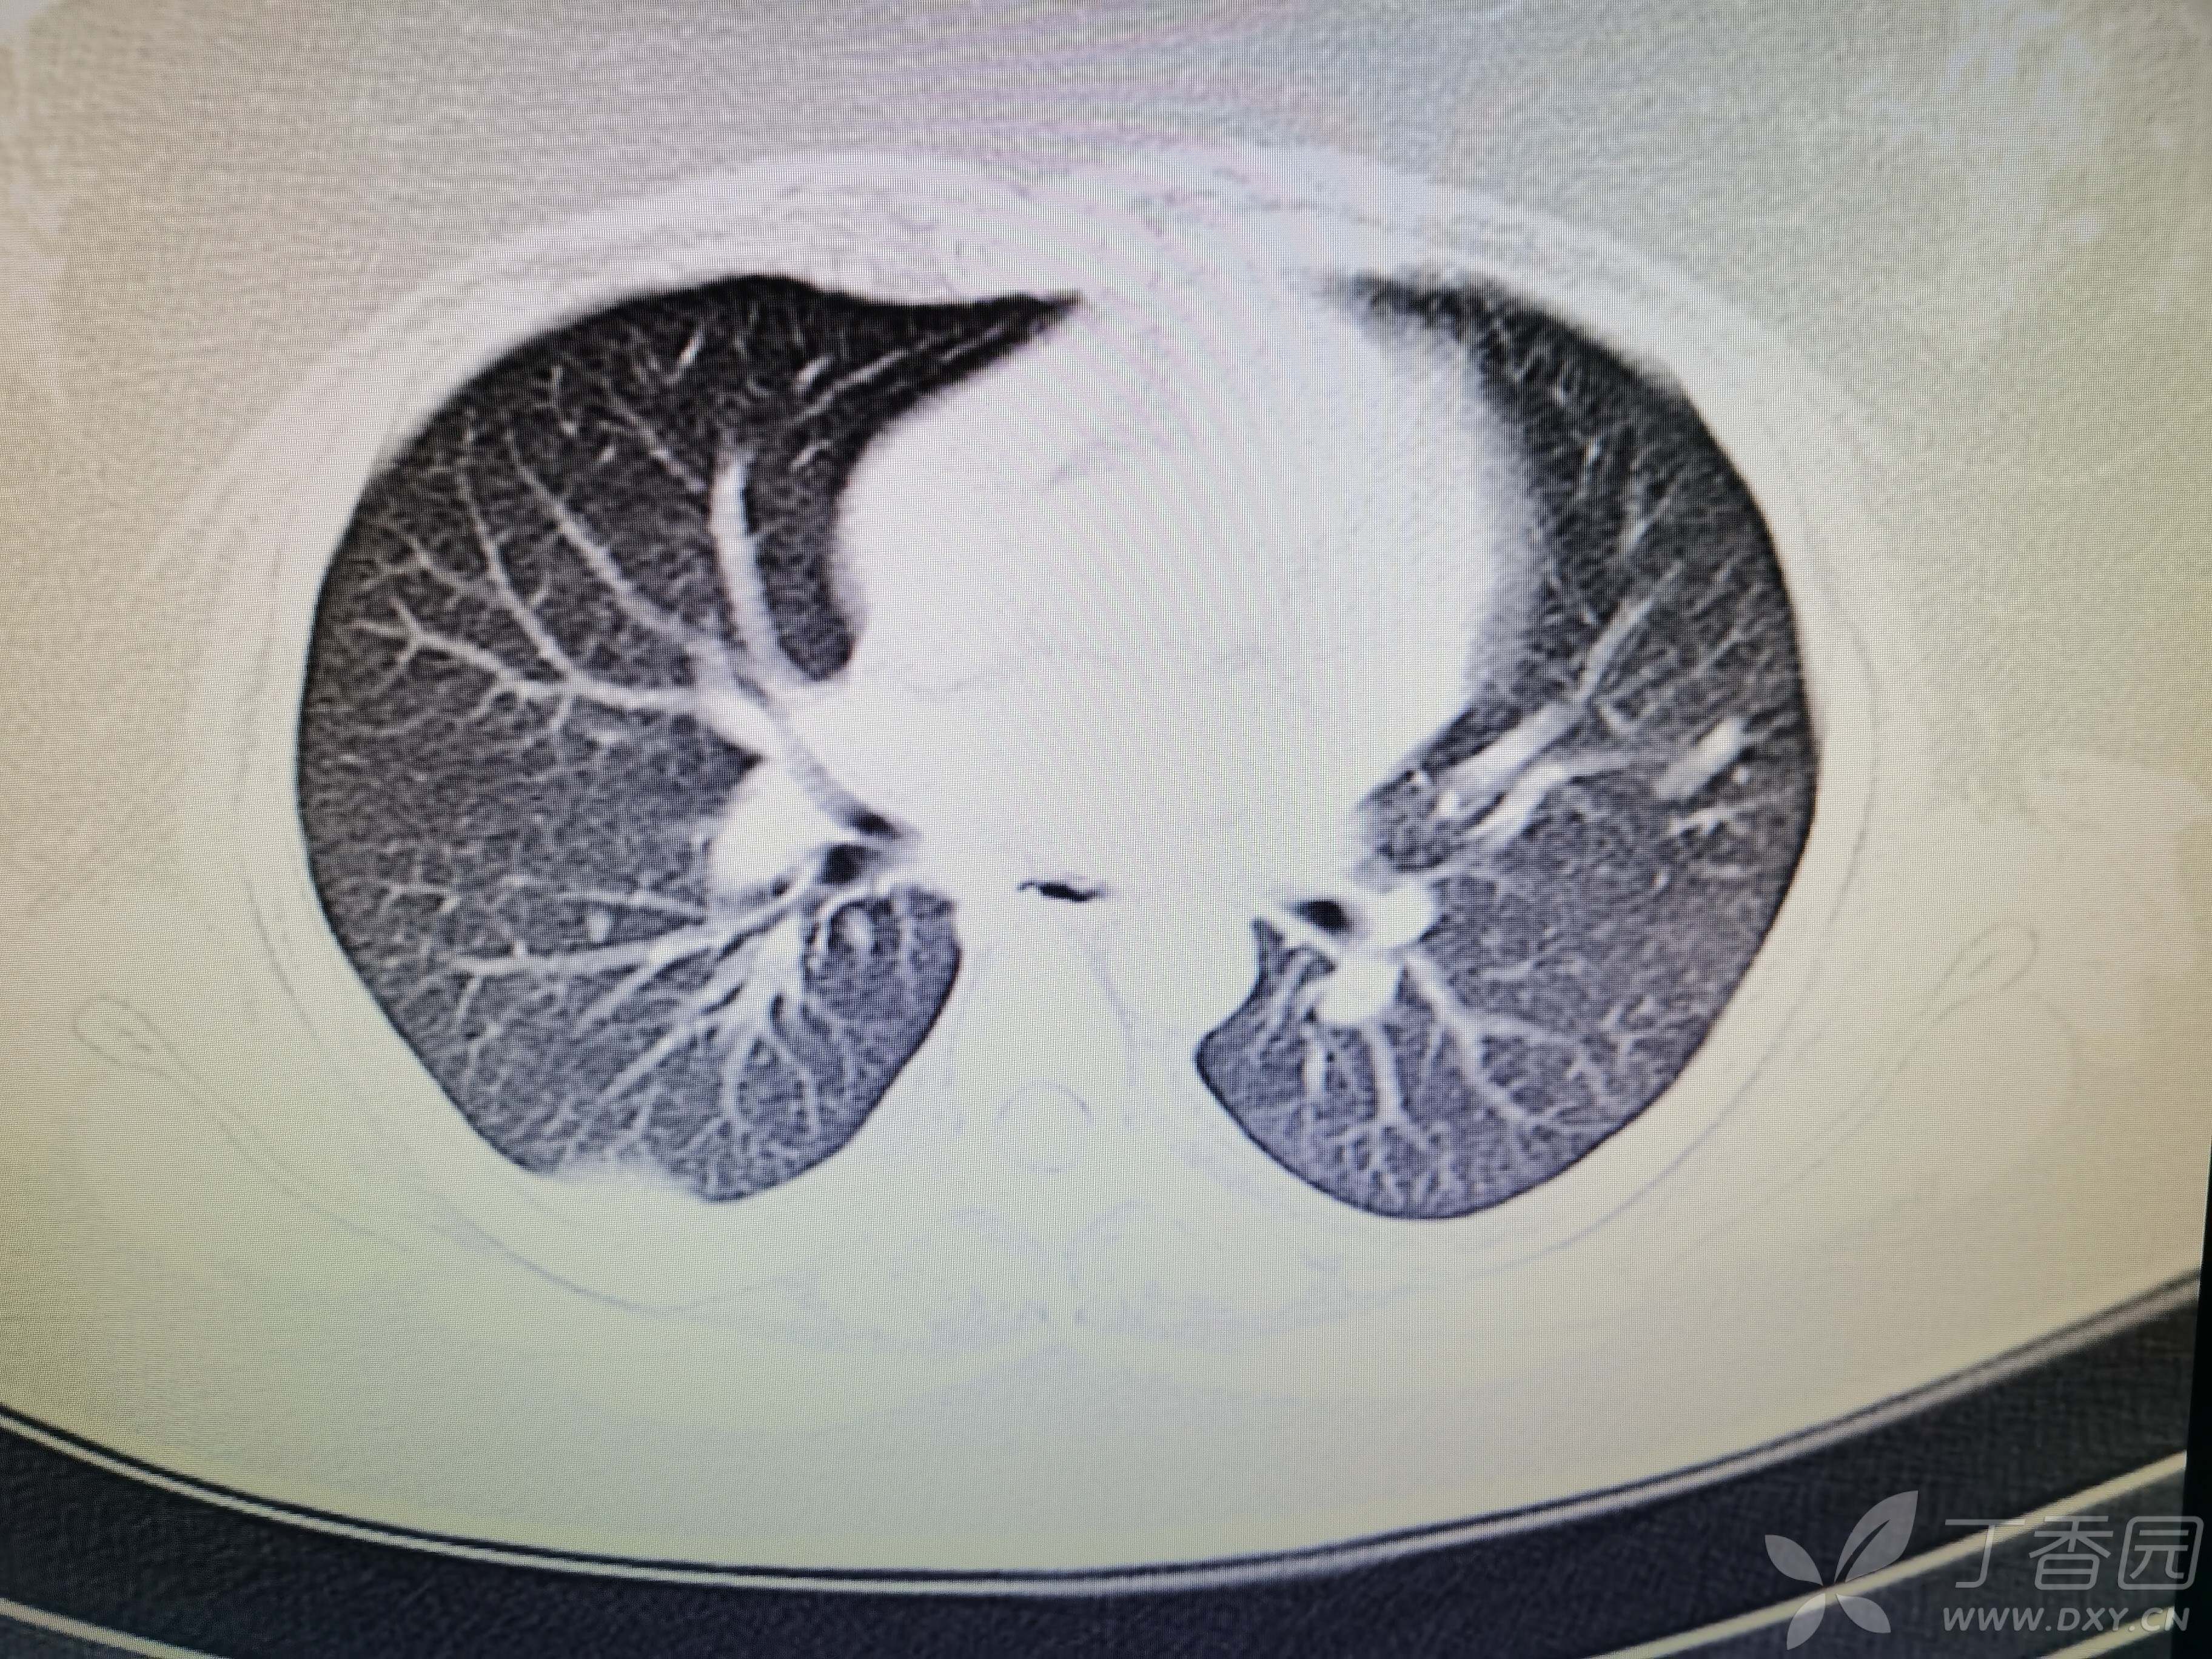

基本信息:女,三十几岁,印度人。。

胸部CT:

如题:猜肺部病灶病理。。